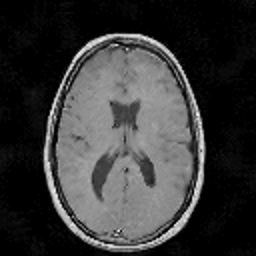

In this subsection, the MRI images from the built-in MRI dataset available in the MATLAB® toolbox have been used as test subjects. Specifically, the denosing algorithms have been tested using the axial slices number 4, 7 and 16 (shown in Figures 5, 5 and 5, respectively), which represent a spectrum of different cerebral structures. For quantitative comparison, simulated data have been obtained by subjecting the original test images to various levels of Rician noise.

Refer to caption

Figure 5: (a) Test slice #4, (b) Test slice #7 and (c) Test slice #16 of the MATLAB® MRI database.